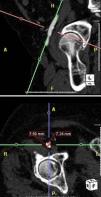

MethodsWe retrospectively analyzed 145 consecutive patients referred to our center for TAVI between March 2007 and October 2011. All patients were assessed by transesophageal echocardiography (TEE) and multidetector computed tomography (MDCT). The aortic annulus diameter obtained by TEE in long-axis view of the left ventricle at 120–140° (Figure 1) was used whenever possible. Minimum iliofemoral diameters were determined by MDCT for the entire segment proximal to the head of the femur, the diameter selected being that of the artery with the most favorable anatomy (Figure 2). The proportion of patients considered suitable for the various devices and approaches was determined according to their respective anatomical requirements (Figure 3).

Determining aortic annulus diameter is an essential step in evaluating candidates for TAVI, since it may immediately exclude a patient from the procedure or dictate the type of device to be implanted. It must therefore be measured accurately, since it determines the choice of the most appropriate prosthesis in each case to minimize the risk of paravalvular leak and device migration.10 There is currently no gold standard exam for annulus measurement, which can be performed by transthoracic echocardiography (TTE), TEE, MDCT or calibrated aortography,10,11 but the few studies comparing the different methods have conflicting results. One limitation of two-dimensional echocardiography is that measurements are based on a single view and assume that the aortic annulus is circular. However, MDTC studies have demonstrated that the annulus is often oval, with significant differences between minimum and maximum diameters.12 In general, the aortic annulus diameter is greater when assessed by MDTC than by TEE, and the latter is in turn greater than that assessed by TTE.10,12–14 In current clinical practice, the eligibility of patients for TAVI and the choice of prosthesis size are generally based on TEE measurement since it is the standard technique and has shown good results.11,13 Recent studies on three-dimensional (3D) imaging have shown a good correlation between measurements obtained by 3D TEE and those assessed by MDCT, which makes echocardiographic assessment a more viable option in these patients.15,16

Another essential step in evaluating these patients is assessment of the peripheral arterial system, which determines the approach to adopt. This can be performed by MDTC, peripheral angiography or magnetic resonance imaging with gadolinium.10 MDTC is a non-invasive technique that provides good quality images of the vascular system through cross-sectional views and 3D reconstructions, which help in procedure planning.10